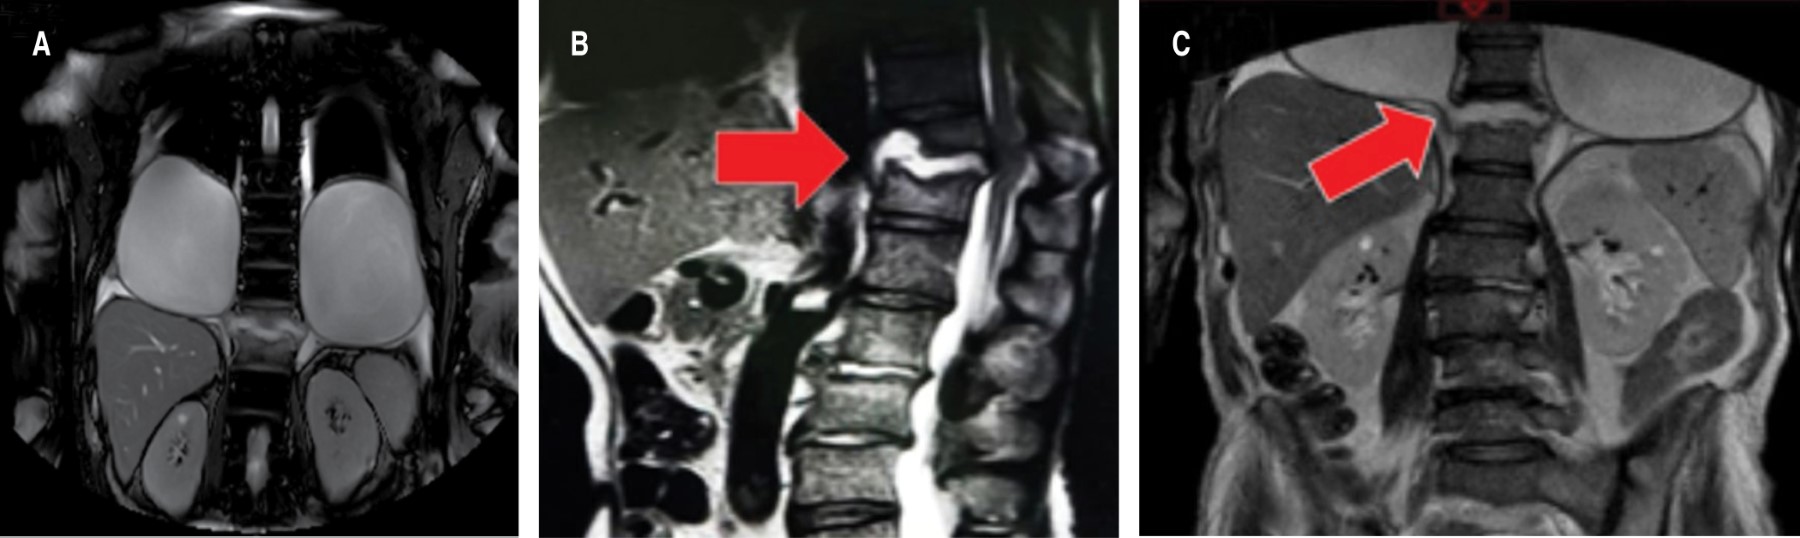

Se realizó resonancia magnética (RM) que documentó, en espacio pleural, imágenes ovales de interior hipointenso en T1, hiperintenso T2 y SPAIR con engrosamiento de pared hasta 11 mm, presentó comunicación con cuerpo vertebral destruido en T12, el cual presentó cambios por espondilodiscitis que condicionó contacto medular y aumento en su amplitud sin cambio en la intensidad (Figura 2).